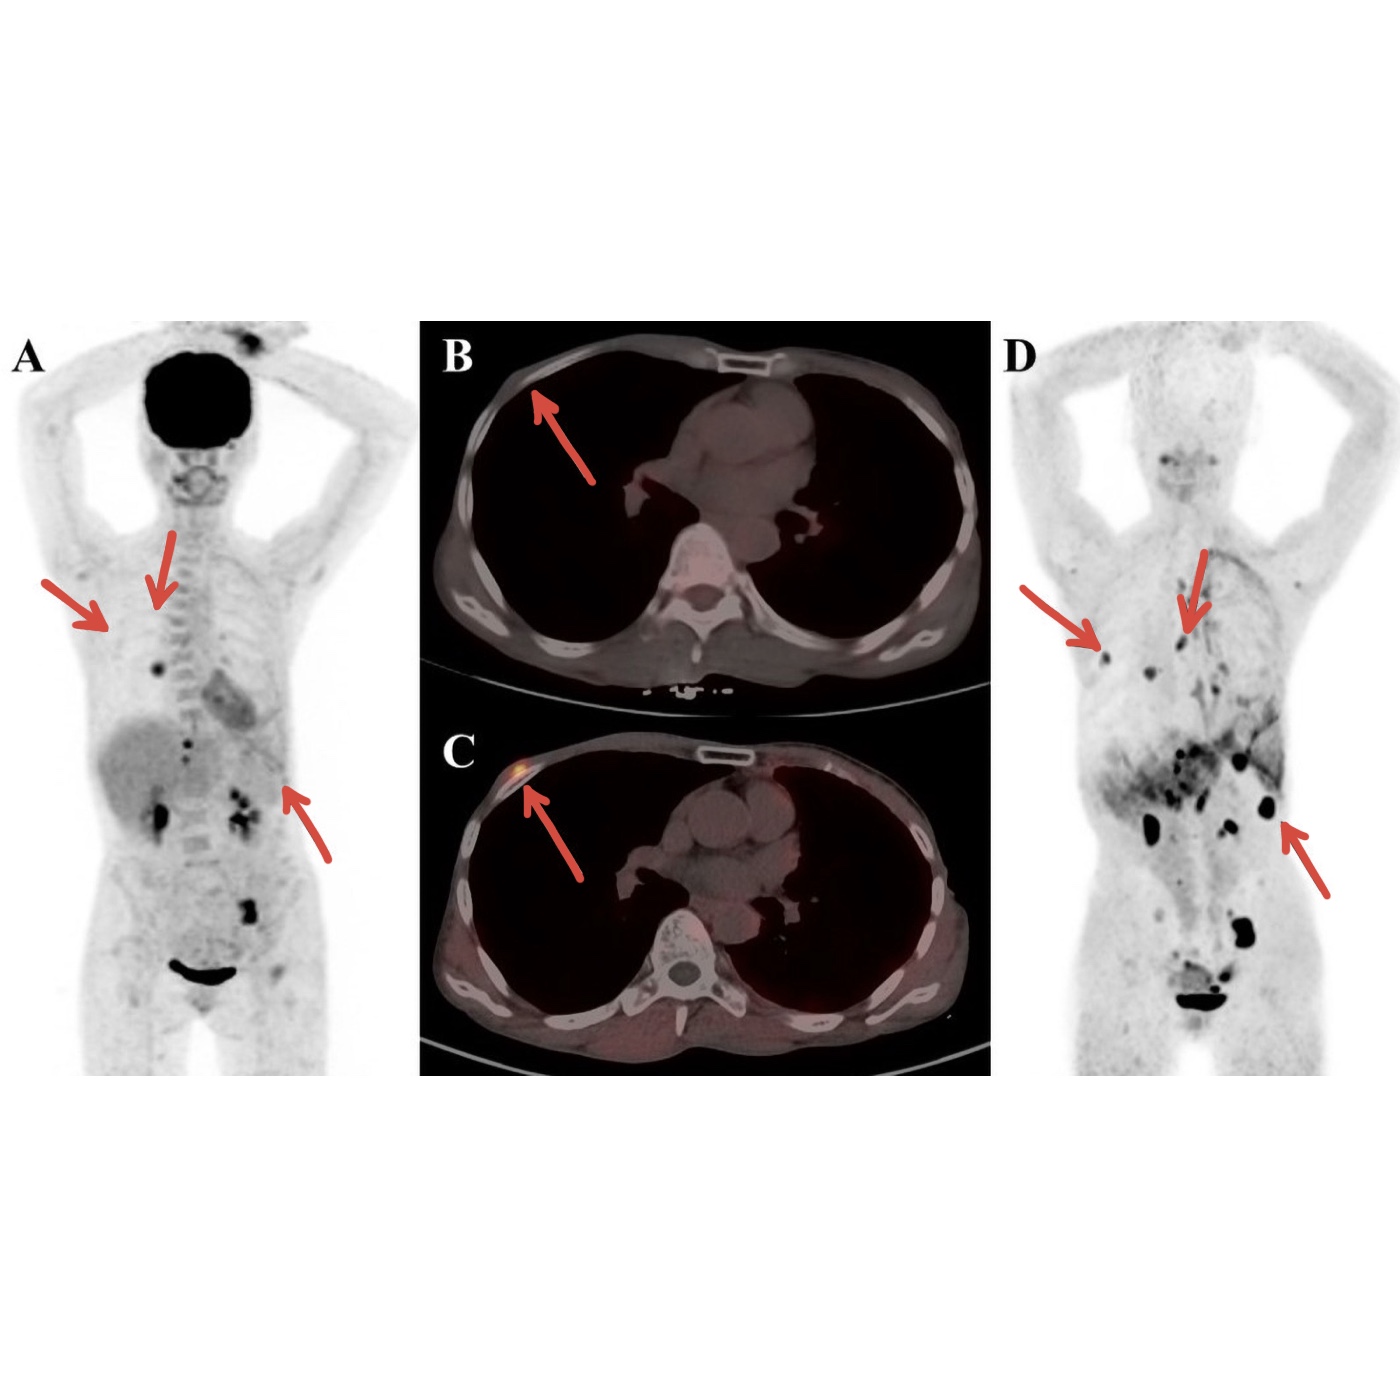

Ab Verabreichung der „Spritze gegen Krebs“ sollte das Immunsystem die Tumorzellen erkennen und bekämpfen können – im gesamten Körper. Das bedeutet: auch Metastasen (bösartige Zellen, die sich in anderen Organen niederlassen und dort gedeihen) werden ebenfalls angegriffen.

Mit Hilfe der PET-CT - Untersuchungen können Metastasen sichtbar gemacht werden. Gehören diese dank der Spritze gegen Krebs bald der Vergangenheit an?

Erinnert Ihr euch noch an die Gedächtniszellen? Diese merken sich die Eigenschaften des „Feindes“, also der Tumorzelle. Kommt es dann zu einem Rezidiv (d.h. die Krebszellen vermehren sich erneut, nachdem sie bereits nicht mehr nachweisbar waren), können diese Gedächtniszellen aktiv werden und den Krebs erneut bekämpfen.